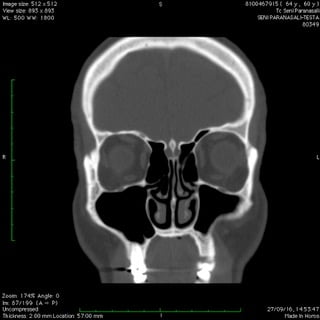

Anche nelle sinusiti la peculiare morfologia anatomica delle strutture coinvolte, cavità ossee, consente nella maggior parte dei casi latenze di esordio molto ritardate rispetto il primitivo insorgere patologico palesandosi così in avanzate fasi di compromissione .

Nelle forme croniche, cioè di malattia stabile nel tempo, i seni paranasali diventano “ siti di decantazione”, ovvero di ristagno e moltiplicazione,per germi di vario genere dando vita così ad un persistente primario serbatoio contaminante sia le vie aeree che quelle digestive.